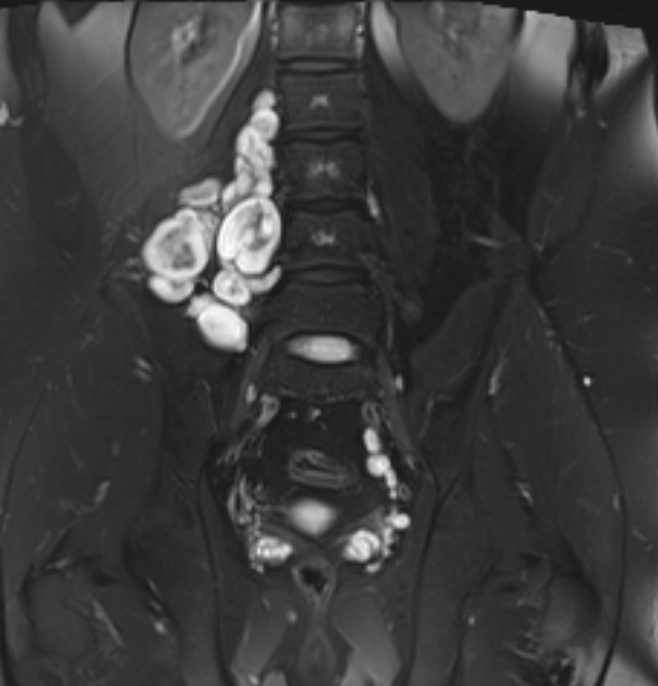

Neurofibroma femoral nerve

Target sign

- hypointense centrally

- hyperintense peripherally